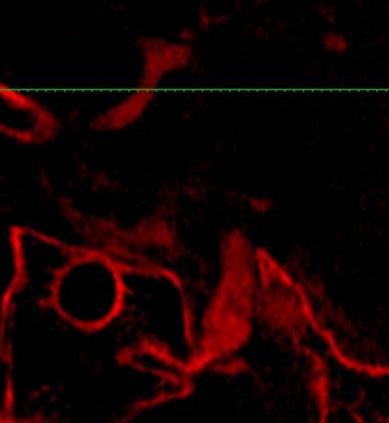

MRI+MRA

脑血管造影提示右侧颈内动脉颅内段多发动脉瘤(反主动脉弓)

脑血管造影提示右侧颈内动脉颅内段多发动脉瘤